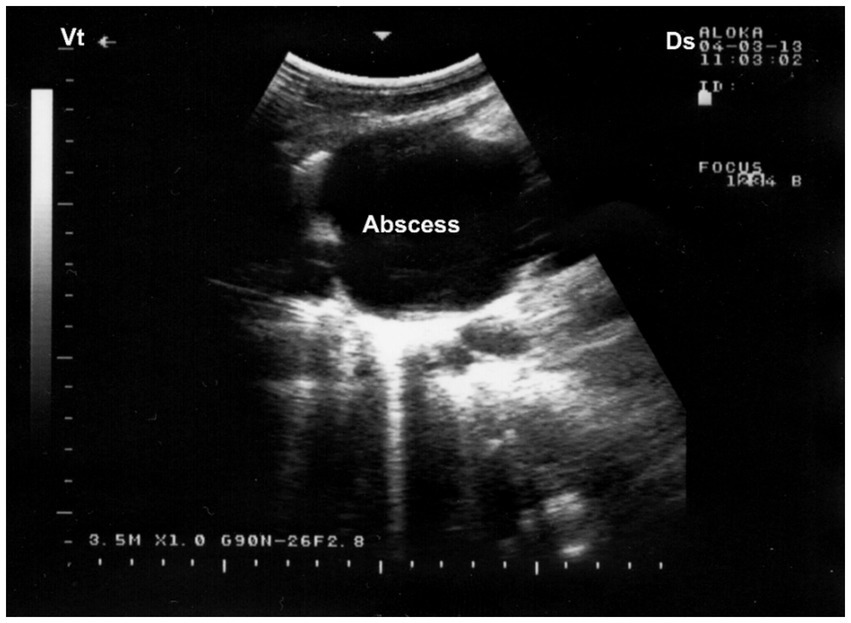

Ultrasonography serves as a valuable diagnostic adjunct in the detection and characterization of pulmonary abscesses, particularly in field settings where radiography is not feasible. Sonographic features typically include well-demarcated hypoechoic to anechoic cavities within consolidated lung tissue, frequently containing internal echogenic material suggestive of purulent content, cellular debris, or necrotic tissue (59). In some cases, gas echoes or reverberation artifacts may be observed within the abscess cavity, indicative of anaerobic infection. The surrounding lung parenchyma often displays hepatization or irregular pleural surfaces, and pleural thickening or adhesions may also be noted (20). In chronic cases, capsulated abscesses may exhibit peripheral vascularization detectable with Doppler ultrasonography, aiding in differentiation from neoplastic or granulomatous lesions. As such, ultrasonography not only facilitates early and non-invasive diagnosis but also provides essential guidance for prognosis, therapeutic planning, and, when applicable, ultrasound-guided drainage or sampling (8). Ultrasonographic examination of the affected lung typically reveals a hyperechogenic pleural surface, pulmonary parenchyma of medium echogenicity, and a heterogeneous pattern resembling liver tissue. Within the compressed lung parenchyma, relatively well-defined abscesses appear as round to ovoid anechoic regions. The abscess capsule is seen as a thin, reflective band, with acoustic enhancement visible beneath the lesion (32) (Figure 10).